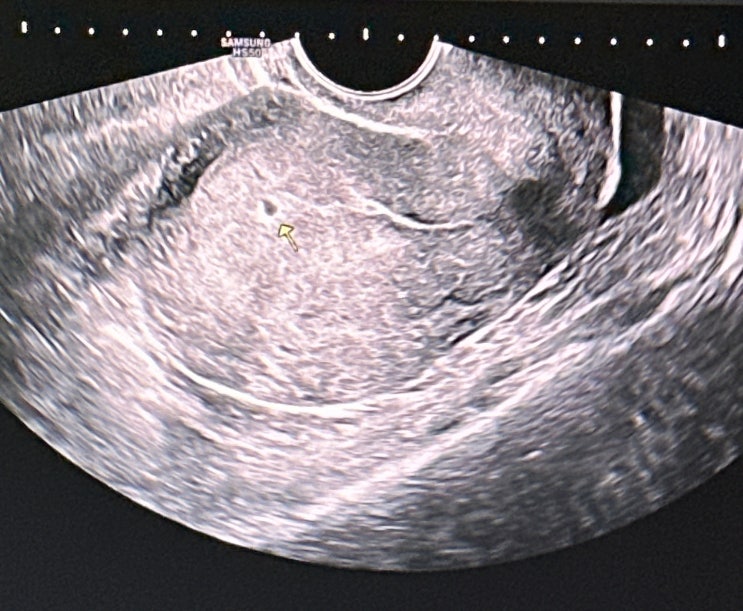

지금까지 별다른 이벤트 없이 우리또리는 무럭무럭 잘크고 있었다 주수보다 작다, 피가 비친다던지 그런일...